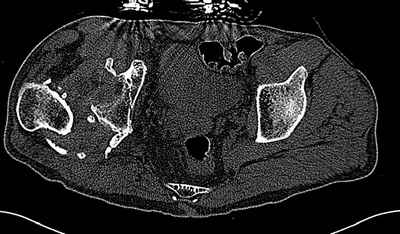

Пациент 30 лет 3 года назад в результате травмы получил травматический

дефект нижних конечностей до в/3 голеней, был пропущен вывих бедра. В настоящее время очень

неплохо ходит на протезах, движения в неоартрозе близки по объему к здоровой стороне.

Основная жалоба - выраженная боль при ходьбе. планируем двухэтапное эндопротезирование -

задним доступом мобилизовать проксимальный отдел бедра, резецировать шейку, аппаратом

низвести бедро(головку оставить там где она есть, так как больших дефектов не видно(может

пригодится в последующем?)). Вторым этапом бесцементное эндопротезирование. Насколько

такой вариант реалистичен? Доступ для второго этапа? Может быть, другие варианты?